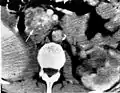

Diagram by Mikael Häggström, M.D.